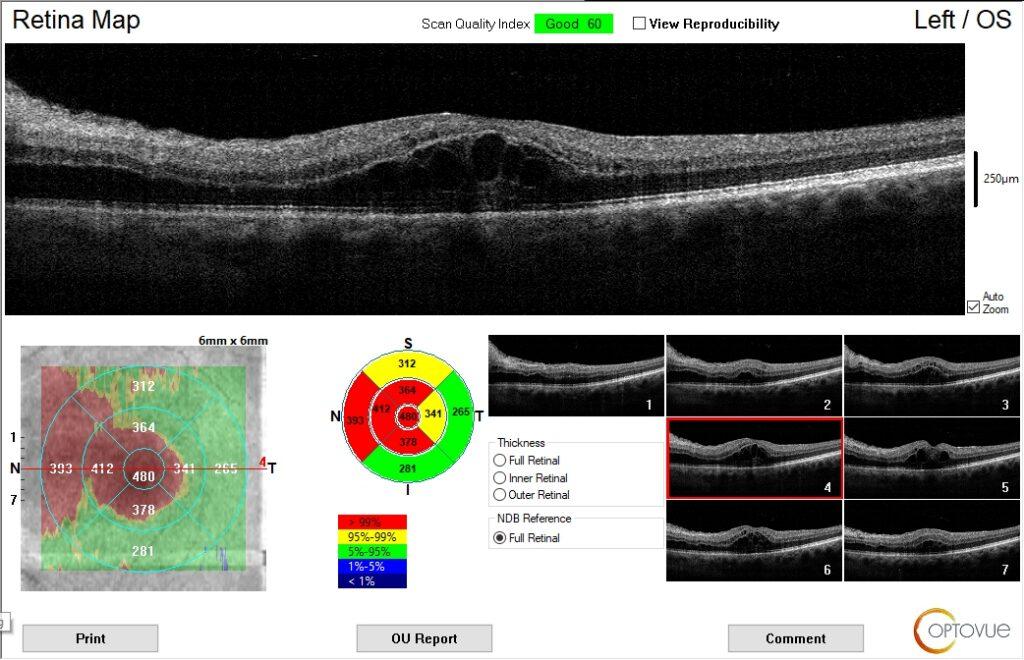

The patient’s entering acuity was 20/20 OD and 20/200 OS. Patient had an APD OS. Fundus examination revealed a few hemorrhages OU due to the patient’s diabetes, optic nerve edema, and macular edema OS. An Optomap fundus photo was taken along with an OCT of the optic nerves and macula.

The patient returned 1 month later. The optic neuropathy and macular edema had resolved. The patient was fitted with new glasses, and acuity was corrected to 20/20 in both eyes. The patient is being managed with ophthalmology and primary care.